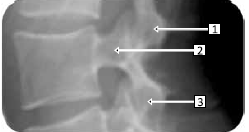

Assinale a alternativa que corretamente descreve as estruturas de uma vértebra, numeradas na imagem abaixo: